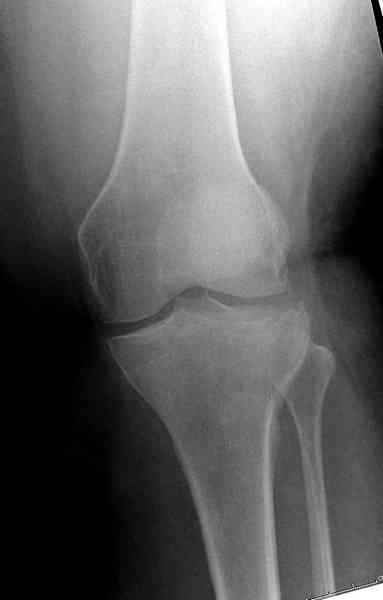

Медиально, обычно на протовоположной

строне, делается окно в кортикальном слое, кривым забойником под рентгеном поднимается импрессия.

Это техника применяется, когда имеется

центральная импрессия, а при ипрессии с краевым переломом - после приподнимания импрессии опорная (Butress) пластина, как на снимке.